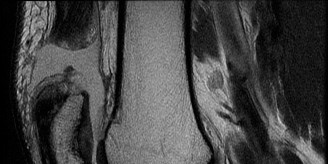

CASE 10 A 24-year-old, ultimate frisbee player reinjures his previously reconst…